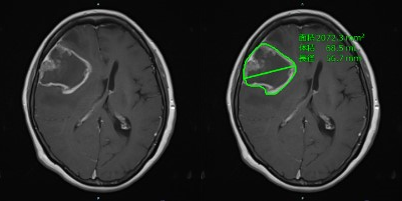

日本國立癌癥研究中心聯手日本富士膠片開發AI技術以提高神經膠質瘤圖像評估的準確性

概述日本國立癌癥研究中心和日本富士膠片株式會社已經共同開發了從MRI圖像中精確提取神經膠質瘤數據的人工智能... -